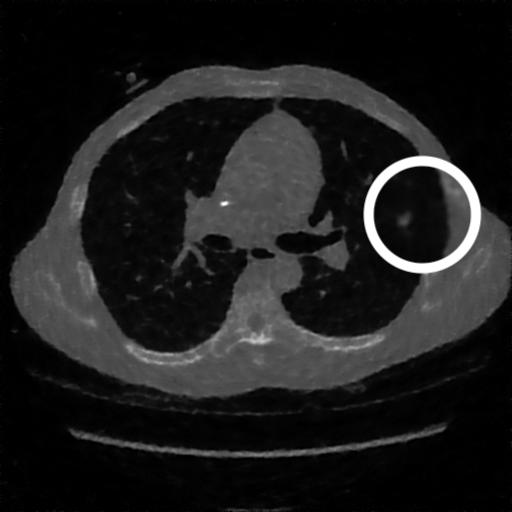

3.1.3 Example 2: data driven reconstruction methods in lung CT screening

There is sufficient evidence that screening for certain tumours using CT images may improve prognosis of cancer survivability (citep \@BBN(Boiselle, 2013)). As mentioned above, in order to gain better image quality with less X-ray dose, many enhanced regularization techniques with integrated machine learning steps have been suggested for CT reconstruction, and in a full reference setting they are commonly evaluated by applying PSNR and SSIM, see e.g. (citep \@BBN(Adler and Öktem, 2018; Hendriksen, Pelt, and Batenburg, 2020; Unal, Ertas, and Yildirim, 2021)). As CT images are generally taken to perform a clinical task, they are not the final step of a medical process but often the initial one. Therefore the definition of what makes a good image heavily depends on the task in hand, and for prognosis related cancer the identification of tumours is of upmost importance.

In on-going research on photon counting detector types and screening procedures for lung cancer (EPSCR grant: EP/W004445/1) an experiment was conducted testing enhanced reconstruction algorithms. Simulations using less than 10% of a clinical X-ray dose were performed to investigate if data-driven methods could sufficiently enhance the images to clearly see the tumours in the lungs while providing very low amount of dosage to the patients. The corresponding data was a CT-dose simulation, using images from the open LIDC-IDRI dataset (citep \@BBN(Armato et al., 2011)) as references, as well as simulated and reconstructed images with in-house software. Figure 3 shows the results of the experiment. We show the reference image used as basis for the simulation, together with five different reconstruction algorithms. The first is an iterative solver, a gradient descend algorithm with TV minimization (citep \@BBN(Sidky et al., 2012)) and (c)-(f) correspond to machine learning methods: FBPConvnet is a denoising algorithm that cleans the bad image (citep \@BBN(Jin et al., 2017)), LPD is an iterative unrolled method that combines traditional solvers with machine learning (citep \@BBN(Adler and Öktem, 2018)), Noise2Inverse is a self-supervised learning method (i.e. does not require ground truth data) (citep \@BBN(Hendriksen et al., 2020)) and ItNet is another iterative unrolled method, the best performing winner of the AAPM DL-Sparse-View CT challenge (citep \@BBN(Genzel, Macdonald, and März, 2021)). ItNet is also judged here as the best result according to PSNR, SSIM and LPIPS.

Refer to caption

(a) Reference

(b) (27.6, 0.70, 0.37)

(c) (31.9, 0.73, 0.29)

(d) (32.5, 0.84, 0.19)

(e) (32.5,0.77, 0.20)

(f) (33.0, 0.89, 0.12)

Figure 3: Reference image (a) and outputs of different reconstruction methods (b)-(f) applied to dose simulated data. PSNR/SSIM/LPIPS are unable to identify the best reconstruction (c), where also the tumour is visualized well.

FR-IQA mismatches

This experiment was performed to evaluate the quality of different kinds of CT reconstruction, and especially the lung tumour detection capabilities thereof. The best result according to the chosen IQA measures is given by ItNet in Figure 3(f), which performs visually poorly. Not only the tumour (zoomed in white circle) is significantly less visible in the reconstruction, but ItNet also produces structures in the lung that are different than the ones in the reference image; it blurs and lengthens much of the soft tissue present in the lungs and it also created structure from noise in some places. Moreover, the image is overly smooth. Comparing the other reconstruction algorithms, it seems that FBPConvnet Figure 3(c) is the one performing best at preserving the shape of the lung nodule, even when the resulting image contains enhanced pixel-level noise.

We can see here that the qualitative findings strongly contradict the numbers provided by the selected measures. The reconstruction of ItNet, Figure 3(f), is outperforming the other reconstructions in regards of the measures, and the qualitative winner FBPConvnet, Figure 3(c), is judged as second worst by the same measures. This experiment suggests that the discussed measures are not a good choice for that kind of CT reconstruction applications and are yielding misleading results.

While pixel-independent random noise may be a worse effect in a natural image than a slightly oversmooth reconstruction, this is not true in CT images, where small structures may disappear if smoothing is promoted against edge preservation. In iterative reconstruction algorithms such choices are explicitly made by choosing the prior appropriately, in data-driven models the researcher has limited control on the type of implicit priors the algorithm learns from the data, i.e. model builders do not know what the algorithms chooses to learn from the ground truth. In these cases appropriate evaluation would therefore be even more important to ensure quality. If this is followed by a blind evaluation using non-appropriate metrics, the promotion of less desirable images can happen, chosen by an implicit assumption on the metric rather than the actual goal of the task.